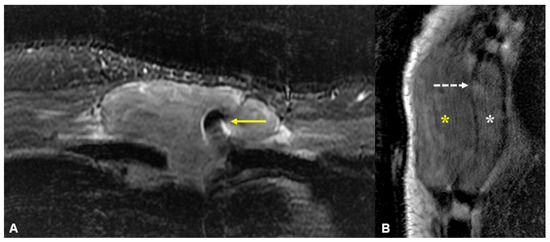

Magnetic resonance imaging (MRI) of the anterior chest wall with selected axial fat-suppressed short-tau inversion recovery (STIR, (A)) and sagittal T1-weighted (B) images. A fairly homogeneous 8.7 cm mass is seen encasing a sternal wire, appearing as focal susceptibility (yellow arrow). The sagittal image shows diffuse marrow infiltration in the deformed and expanded sternal body (white asterisk) with a large extra-osseous mass extending into the anterior soft tissues (yellow asterisk) through a relatively preserved cortex (linear hypointense signal indicated by the dotted white arrow). While this appearance has been described in osseous lymphoma [2], it can also occur in other malignant round cell lesions of bone, including plasma cell neoplasms [3]. This is likely due to permeative tumour growth via cortical neurovascular channels, allowing relative cortical preservation despite the large extra-osseous component. Other differentials for this MRI appearance include Ewing sarcoma or primitive neuroectodermal tumour (PNET), but these occur predominantly in the paediatric population. Histological evaluation of the lesion revealed a plasma-cell-rich lesion with occasional plasma cells demonstrating nuclear atypia and plasmablastic-type morphology. The plasma cells also show evidence of kappa immunoglobulin light chain restriction using in situ hybridization techniques. Bone marrow biopsy demonstrated an infiltrate of neoplastic plasma cells within the intertrabecular spaces, comprising 60% of the nucleated cell population. Further laboratory investigations revealed elevated total serum protein levels of 105 g/L (normal range 65–82 g/L), with a kappa free light chain (FLC) level of 256.7 mg/L (normal range 3.3–19.4 mg/L) and free kappa-lambda ratio of 42.08 (normal range 0.26–1.65). The IgG level was 53.2 g/L (normal range 5.0–15.0 g/L) and B2-microglobulin level was 5.59 mg/L (normal range 0–1.9 mg/L). Cutaneous plasmacytomas have been known to develop at sites of previous surgery or trauma, whether as a secondary lesion in patients with known plasma cell disorders [4,5] or as a primary lesion [6,7]. However, we believe that this is the first description of a primary plasma cell disorder presenting with both osseous and extramedullary disease at the site of previous sternotomy. The predilection of plasma cell neoplasms for sites of injury or scar formation is not well understood. It has been postulated that the inflammatory mediators present in scar tissue to facilitate wound healing (such as interleukin-6, interleukin-8, and tumour growth factor-β) can result in the selection of a clonal plasma cell population and also support tumour growth and survival [5,7].